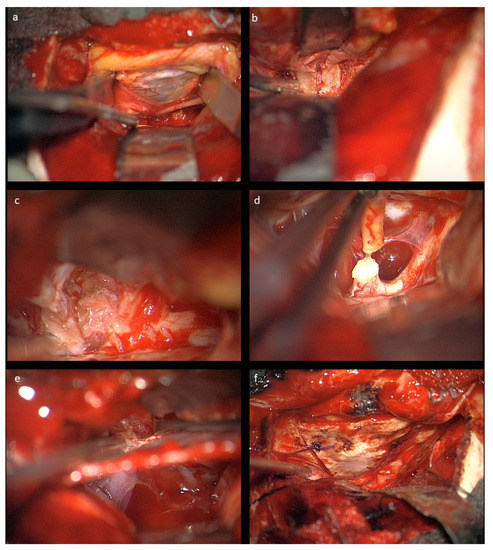

In Tuebingen (Group A), a fronto-temporal skin incision was used, followed by supraorbital craniotomy. After epidural exposition of the orbit, its roof is opened by osteotomy and the optic canal is unroofed with a diamond drill back to the dural fold. The anterior clinoid process is not drilled, and care is taken not to open the ethmoidal cells medial of the optic canal. After T-shape opening of the periorbital fascia, the frontal branch of the first trigeminal nerve and the superior rectus muscle/levator palpebrae muscle are dissected and retracted laterally, including the superior oculomotor branches entering the muscle from below, in order to expose the tumor. The abducens nerve is not encountered during this approach.

The nasociliary nerve crossing the optic nerve in the middle of the orbit and the trochlear nerve crossing close to the conus are identified to avoid injury during resection. Then, the dura of the optic nerve sheath covering the tumor is opened and an intradural tumor resection is performed, directed anteriorly following the nerve sheath, until the eye bulb is reached. Inside of the dura, no relevant neurovascular structures are encountered. Great care is taken not to injure the eye bulb at the level of optic nerve transection as close to the bulbus as possible. Then, the tumor is followed posteriorly within the optic nerve sheath towards the optic canal. The muscle attachment of the superior muscles at the orbital cone needs to be spared as well as injury to the visible trochlear nerve avoided. Then, the intradural resection is continued behind the muscle attachment within the optic canal towards the intracranial cavity until CSF comes from the intradural compartment. At this point, the dura is opened in a straight line at the level of the skull base; the intradural optic nerve, chiasm, and carotid artery are dissected; and the optic nerve is transected between the visible end of the tumor and chiasm. In the case of tumor extension close to or immediately at the chiasm, care must be taken not to enter the latter to avoid any injury of crossing fibers. The remaining tumor part in the junction area of the extradural optic canal and the intradural compartment just above the carotid and ophthalmic artery is carefully mobilized from its attachments using the intra- and extradural route and finally removed. The ophthalmic artery can be visualized in the first millimeter intradurally; the dissection at this transition zone has to be performed very carefully and without force, and this way injury to the artery is avoided. The artery can also be seen at the very beginning of the optic canal after tumor removal, but mainly runs behind the dural optic nerve sheath, and is thus not endangered there, just as the inferior oculomotor branches intraorbitally. The optic canal is plugged with muscle fixed with fibrin glue, and then the periorbital fascia is reconstructed with 6-0 sutures. The bone of the orbital roof is replaced and fixed with PDS sutures, and the dura closed thereafter. The craniotomy is refixed with PDS sutures in children below 15 years, otherwise titanium plates are used. Intraoperative photographs are provided in Figure 2.

Figure 2. Intraoperative microscopic view after left-sided craniotomy: (a) The optic roof was removed and the periorbita is visualized; the frontal nerve (V1) is seen under the retractor. (b) The optic canal is visualized extradurally. (c) Resection of the glioma in the optic nerve sheath intraorbitally. (d) Transection of the optic nerve prechiasmatically. (e) Combined intra- and extradural visualization of the optic canal and the intradural space medial to the carotid aretery. At the bottom of the optic canal, the beginning of the ophthalmic artery can be seen. (f) Reconstructed orbital roof.